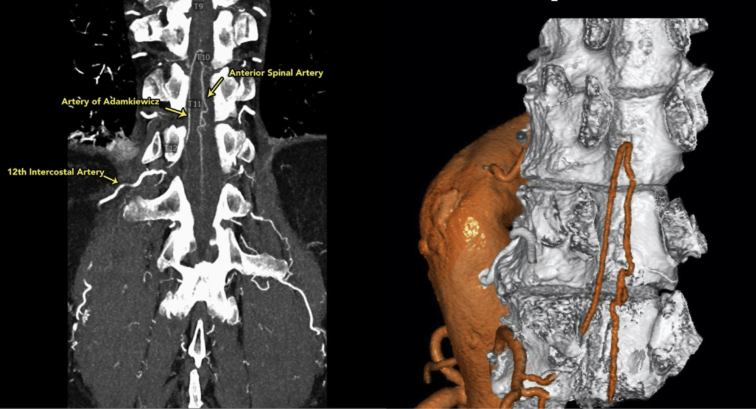

Three-dimensional reconstruction of the anterior spinal artery (T12) using the dual-intensity Yale technique.

CTA of the chest and abdomen were performed during infusion of iodinated contrast material and after administration of sublingual nitroglycerine (Figure 1). We scanned patients with a high-resolution or dual-energy technique based on patient size and also instrumental availability. A high-spatial resolution time-resolved technique was used. Earlier in the series, occasional patients underwent magnetic resonance imaging or MRA instead of CTA. We did not evaluate the patency of reconstructed spinal arteries postoperatively.9

Figure 1.

Visualization and 3-dimensional reconstruction of the anterior spinal artery (ASA) using a special dual-intensity Yale technique, which is part of our standard spinal cord protection regimen. The artery of Adamkiewicz is shown, arising from the 12th intercostal artery and joining the ASA.

We thank Drs Hamid Mojibian and Steffen Huber from Yale Radiology and Biomedical imaging for providing us with the CT scan and 3-dimensional construction of the anterior spinal artery for the central picture.